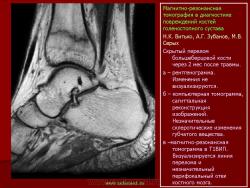

Магнитнорезонансная томография в диагностике повреждений костей голеностопного сустава.

Стрессовые переломы возникают при многократном давлении на кость с величиной, не достигающей критического значения, чтобы привести к острому перелому. Патофизиологически они обусловлены быстрой адаптацией мышц к нагрузке и недостаточной адаптацией к стрессу костей.

Семиотика стресс-переломов аналогична скрытым переломам костей голеностопного сустава и стопы. Дополнительно визуализируется периостальная реакция. Однако в отличие от скрытых переломов патологические изменения визуализируются и рентгенологически.

При проведении МРТ больным с переломами костей голеностопного сустава и стопы не ставится задача оценки переломов. Изучается состояние сухожильно-связочного аппарата и параартикулярных мягких тканей. Гипсовые повязки не оказывают существенного влияния на качество и информативность изображений.